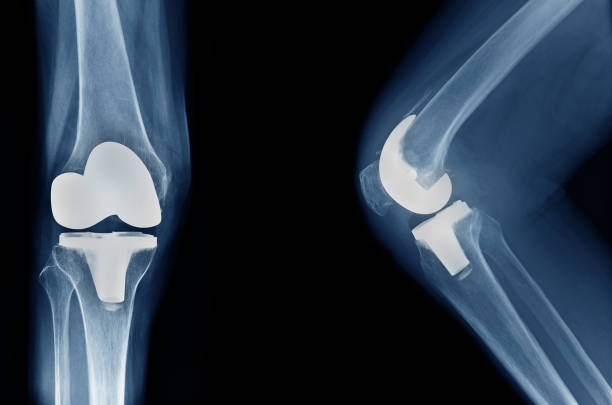

Advanced Joint Replacement Surgery in Noida

When it comes to joint replacement surgery, ShardaCare – Healthcity is your trusted partner. We offer expert Knee Replacement Surgery, Hip Replacement Surgery, and Ankle Replacement Surgery in Noida to help you regain your mobility and reduce pain. Our highly skilled surgeons use advanced techniques to perform joint replacements, minimising downtime and accelerating recovery.